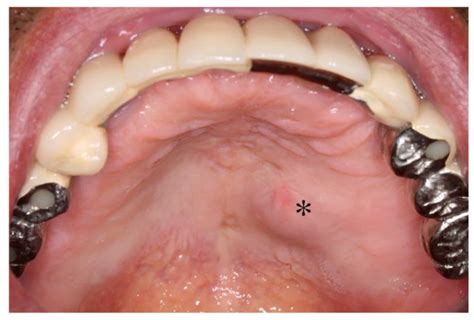

Diagnosing a Swollen Mouth Palate

Diagnosing the cause of a swollen mouth palate typically involves a combination of physical examination and medical history. A healthcare provider may perform the following steps:

• Visual inspection of the mouth and throat.

• Palpation of the neck and jaw to check for swelling or tenderness.

• Review of medical history, including any recent illnesses, injuries, or medications.

• Blood tests to check for infections or autoimmune disorders.

• Imaging studies, such as X-rays or CT scans, to identify underlying dental issues.